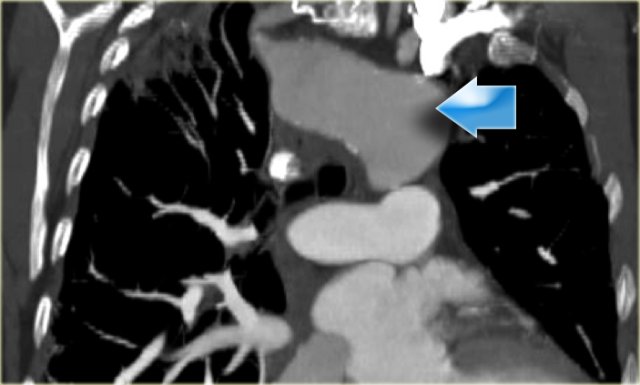

Dysphagia lusoria in patient with dilated aberrant right subclavian artery. Dysphagia lusoria in patient with dilated aberrant right subclavian artery.

Only rarely these patients become dysphagic (dysphagia lusoria) , when the origin of the right subclavian artery becomes dilated.

On a barium study of the esophagus you will see a posterior impression with an oblique course directed towards the right shoulder.

On the left a 78 year old woman with dysphagia.

There is consolidation in the right upper lobe, maybe due to aspiration.

There is a dilated vessel that compresses the esophagus and it originates from the left-sided aorta, i.e. an aberrant right subclavian artery.

On the left the same patient with dilated aberrant right subclavian artery.

Coronal reconstruction.